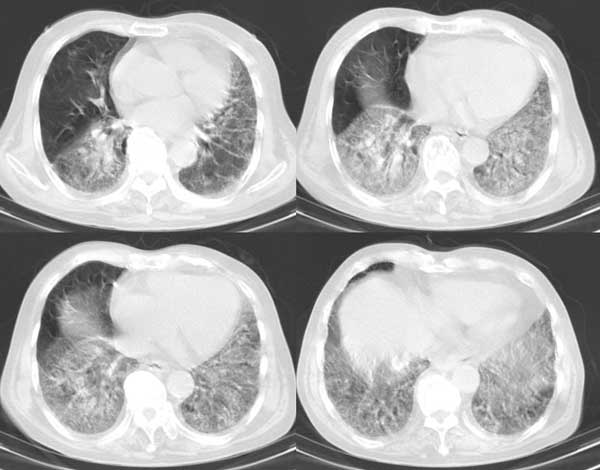

以下是引用dalianren在2006-7-20 21:23:00的发言:[br]我考虑是肺泡蛋白沉积症:典型表现为两肺内散在片状\"磨玻璃\"样混浊区呈地图样分布.

以下是引用lj0804在2006-7-21 12:57:00的发言:[br]支持[br]我考虑是肺泡蛋白沉积症:典型表现为两肺内散在片状\"磨玻璃\"样混浊去呈地图样分布.